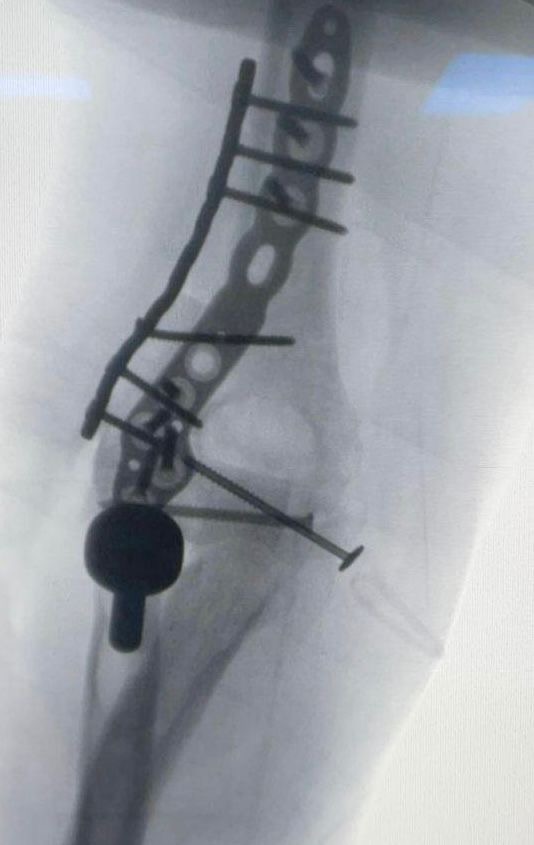

في إنجاز طبي يعد الأول من نوعه على مستوى المنطقة الشرقية، نجح فريق طبي في مستشفى الملك فهد الجامعي بالخبر – التابع للمدينة الطبية الأكاديمية بجامعة الإمام عبدالرحمن بن فيصل – في إجراء عملية جراحية نادرة ومعقدة، تمثلت في زراعة مفصل المرفق وترميم الأربطة المحيطة لشاب في مقتبل العمر، بعد أن تعرّض لإصابة خطيرة نتج عنها كسر مضاعف وفقدان جزء كبير من المفصل وتهتك في الأنسجة المحيطة.

قاد الفريق الطبي للعملية الدكتور سعد القحطاني – رئيس قسم العظام واستشاري جراحة العظام والأطراف العلوية – حيث أوضح أن الفريق تعامل مع الحالة منذ بدايتها بشكل دقيق، بدءًا من فحص المريض في العيادة وإجراء الفحوصات المخبرية والأشعات ، وصولًا إلى التعاون مع الدكتور محمد بارجاء من قسم الهندسة الطبية الحيوية للاستعانة بتقنية الطباعة ثلاثية الأبعاد في تحديد حجم الجزء المفقود من المفصل بدقة عالية.

وأشار الدكتور القحطاني إلى أن مثل هذه الحالات غالبًا ما يتم علاجها عبر تركيب مفصل صناعي، إلا أن صغر سن المريض جعل الفريق يتخذ قرارًا استثنائيًا بزرع عظم ومفصل من متبرع ، مع ترميم الأربطة المحيطة للمفصل، بهدف الحفاظ على وظيفة المرفق ومنح المريض أفضل نتيجة ممكنة.